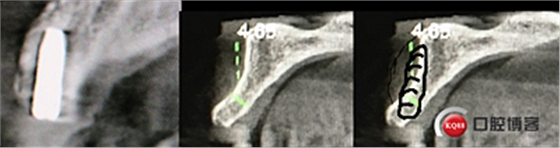

“以修復為導向”,在前牙種植體中心點就是未來牙冠舌側(cè)窩位置。那這個病例植體的方向和位置就只能是下圖右側(cè)這樣了。很明顯植體根尖部分要穿出唇側(cè)倒凹的。怎么辦?翻大瓣植骨蓋膜減張縫合?不!可以不翻瓣,大家仔細看看下圖右圖我畫的那條細細的弧線,是不是跟原來唇側(cè)凹陷的骨面成為左右對稱的兩條弧,也就是說骨膜從原來唇側(cè)凹陷骨面上剝離然后放到左側(cè)我畫的那條弧線那里根本不需要減張,這兩條弧線之間也就是唇側(cè)凹陷處放上骨粉,骨膜不會增加張力。不知道大家看明白了沒有。

術后4個月X光片。